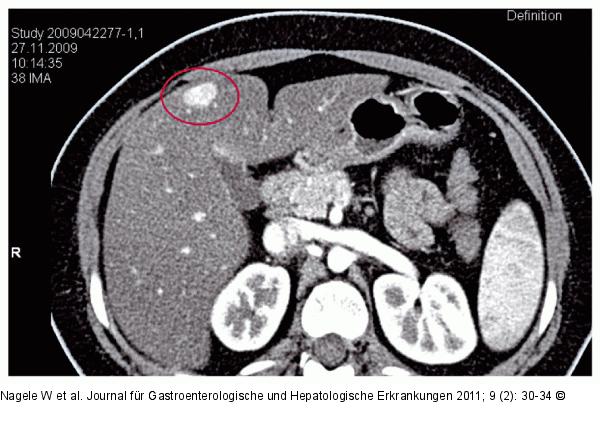

Abbildung 3: CT des Oberbauchs mit Kontrastmittel CT des Oberbauchs mit Kontrastmittel: In der portalvenösen Phase homogene Kontrastmittelanfärbung eines Pelioseherdes im Lebersegment 4b. |